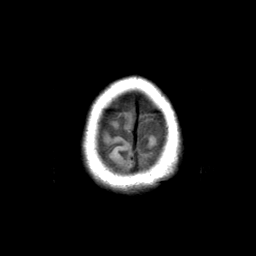

Basal Ganglia Calcification: T1-weighted MR -- Slice #17

[Home][Help][Clinical] Slice 17